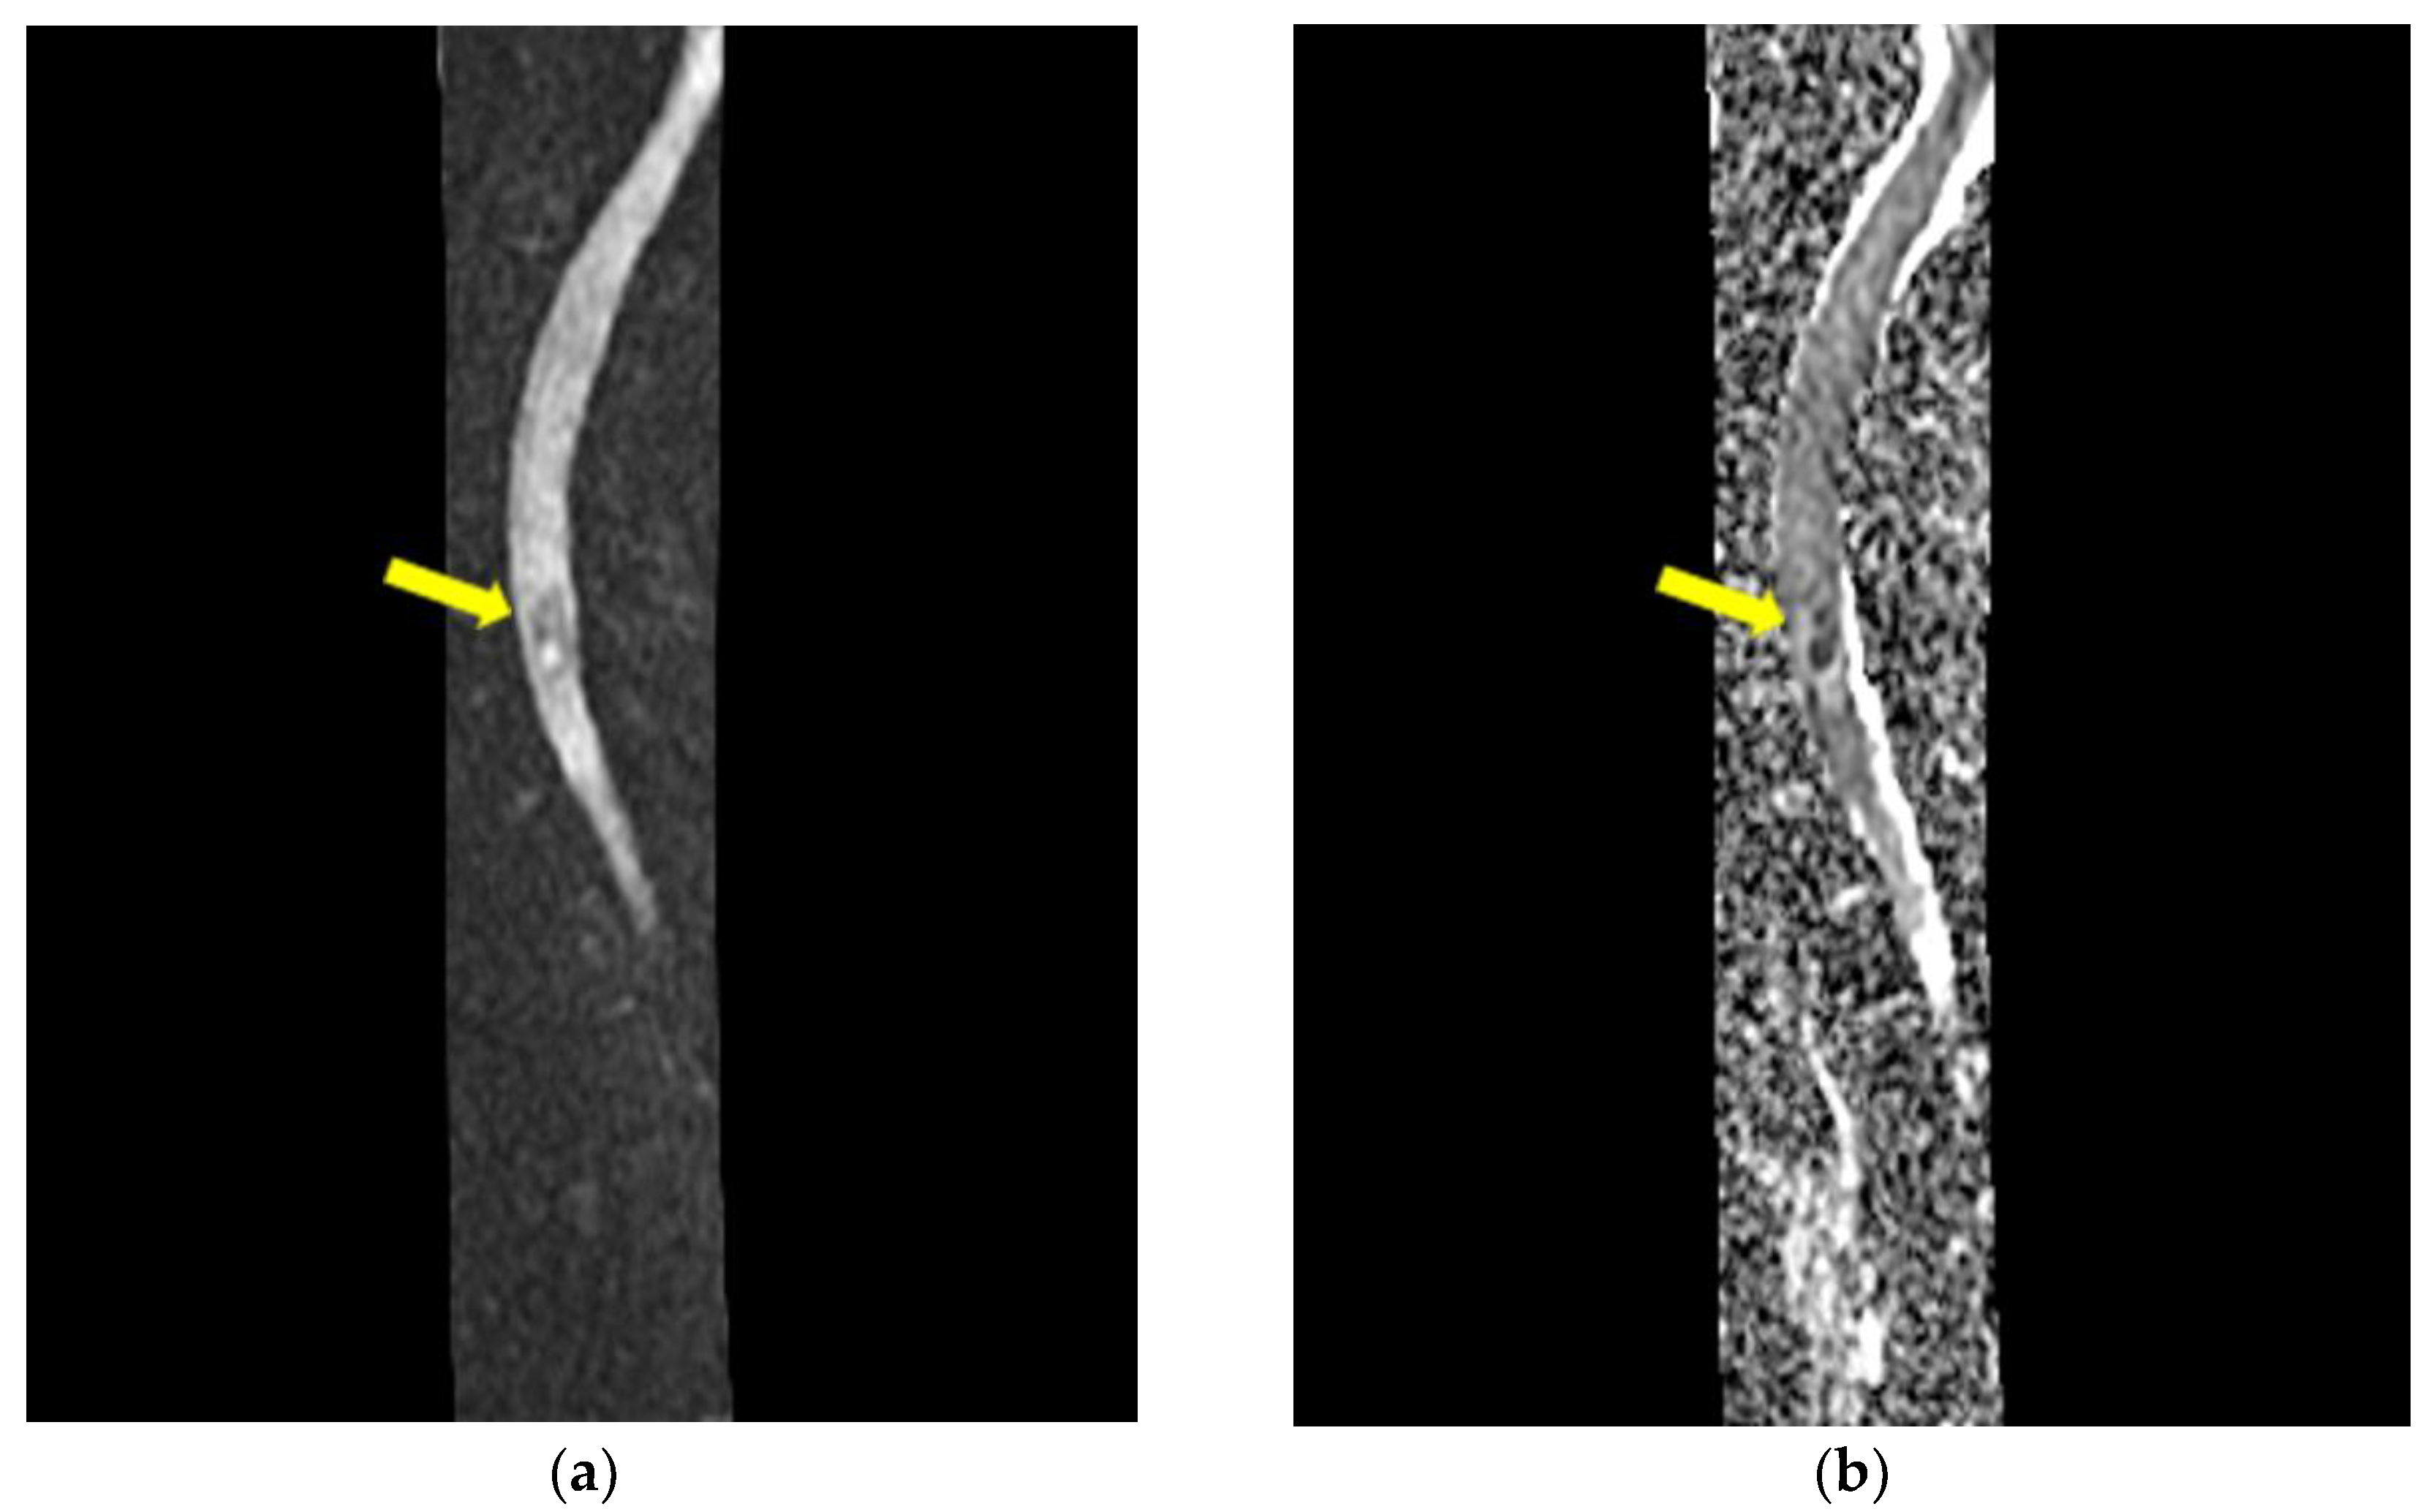

2. Detailed Case Description

- Mycological demonstration of Aspergillus fumigates hyphae by microscopy from spu-tum, microscopy and culture from bronchial aspirate, and histopathological evi-dence of the presence of Aspergillus fumigates hyphae with dichotomous branching in the spinal cord biopsy;